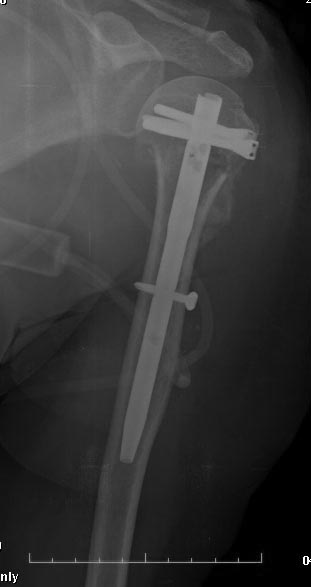

Любой вид остеосинтеза нужно "оставить" тем, кто знает и умеет его использовать. Когда чего-то не умеешь, легче всего выказать пренебрежительное отношение - мол, это можно оставить им, мы-то по-другому. НаучИтесь - понравится. Вот примерчик, операция закрыто через 2 мес. после травмы.

Действительно, Multiloc сегодня лучший. Но дело не в конкретной модификации PHN. Вся проблема в обсуждаемом случае в отличной перспективе закрытой репозиции, которую жаль упускать. Сделать хорошую репозицию руками и джойстиками трудно, а дистрактор правильный мало кто применяет.

Речь не о вообще любых, или всех, переломах в этой области, а о конкретном этом случае (и подобных) - хирургическая шейка, большой бугорок не смещен. Когда действительно нужна открытая репозиция - это совсем другая история, и нет, очевидно, большой разницы, чем в итоге зафиксировали, еще и эндопротез бывает нужен. А тут - несколько разрезиков по 1 см, операция 20-30 мин. И между "минимальным смещением" и "3-4 фрагментах и значительном смещении" помещается много чего, вот как раз типа этого случая и того, что я показал.